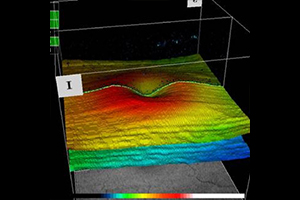

Der optische Schnitt einer normalen Netzhaut

Die untere Abbildung zeigt einen Schnitt durch die Netzhautmitte (Makula) mit der wichtigen Stelle für das Scharfsehen - die Sehgrube (Fovea). Die Einsenkung stellt den Normalbefund dar, welches in der dreidimensionalen Bildgebung besonders gut veranschaulicht wird.

normaler Netzhautbefund - OCT

3D Darstellung- OCT